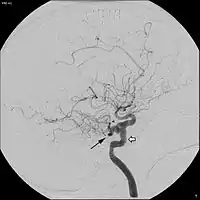

Корінець трійчастого нерва кровопостачається двома-шістьма гілочками, які можуть відходити як від основної артерії, так і від її гілок: верхньобічної мостової артерії (лат. arteria pontina superolateralis), нижньобічної мостової артерії (лат. arteria pontina inferoposterior), задньобічної мостової артерії (лат. arteria pontina posterolateralis), передньої нижньої мозочкової (лат. arteria cerebellaris inferior anterior), верхньої мозочкової (лат. arteria cerebellaris superior) та трійчастої (лат. arteria trigeminalis). Остання артерія є залишком ембріональної системи кровообігу головного мозку і часто (якщо наявна) спричиняє компресію нерву, і тому розглядається як одна з причин невралгії трійчастого нерва.[50][51]